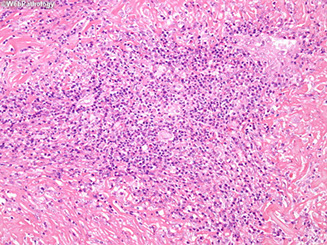

Chronic lymphocytic (autoimmune) thyroiditis

- aka Hashimoto's thyroiditis (HT)

MCC hypothyroidism and thyroiditis; almost exclusively in perimenopausal women

- autoimmune dz (antithyroid and antimicrosomal antibodies) where follicles destroyed by T cells (CD4+ T cell activation c formation of cytotoxic CD8+ cells), causing pt to become hypothyroid

- grossly enlarged, symmetrical

Gross: pale-white, rubbery thyroid

anti-TSH-R ab's made by germinal center B cells

- antimicrosomal and antithyroglobulin abs

- HLA-DR5 assoc

Thyroid cell death from 1) TH1 cells, 2) IFN-gamma secreted by TH1 cells activates macrophages, 3) ab's cause ADCC

Micro: lymphocytic infiltrate c germinal center and plasma cells; Hurthle cells (enlarged epithelial cells c eosinophilic granular cytoplasm)

- extensive oncocytic change

Tx: levothyroxine (for life); surgery if does not regress

Px: inc risk autoimmune dz and B-cell non-Hodgkin lymphoma (usually B-cell [DLBCL], extranodal marginal zone B-cell lymphoma (MZL) and mixed DLBCL / MZL), papillary ca and Hurthle cell neoplasms

- can possibly lead to atrophy of thyroid